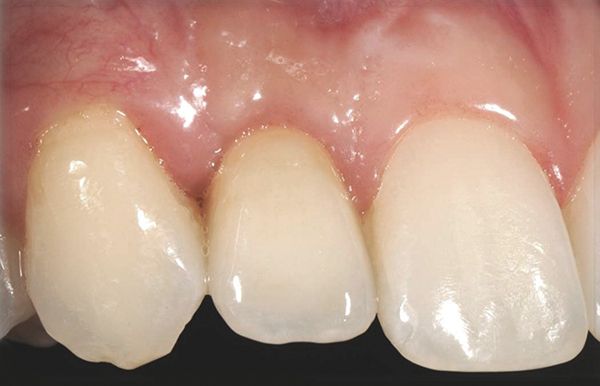

Fig 10. Case 2: Missing tooth No. 7 was extracted 3 months before implant placement.